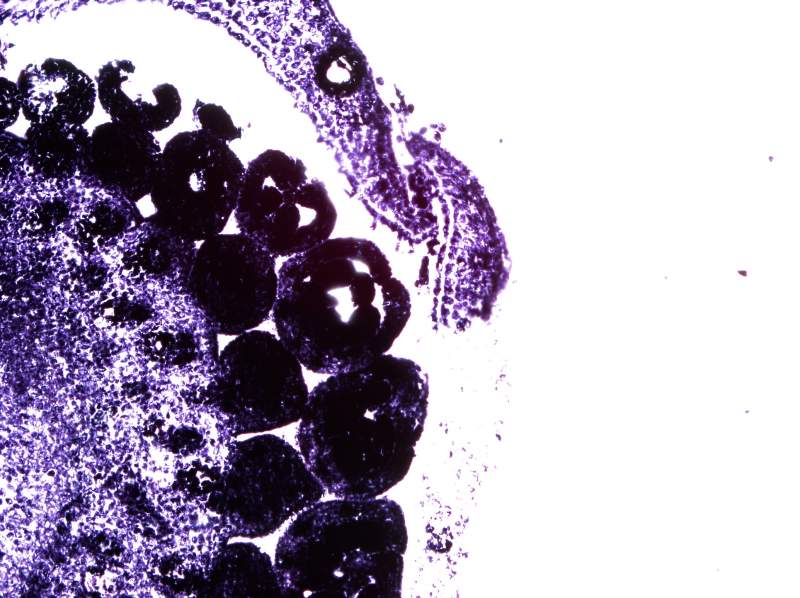

°¥£¬ËùÒÔºËÐļ¼Êõ»¹ÊÇÒª×Ô¼ºÕÆÎÕ²ÅÐÐ PSÓÖ²»ÊÇ×÷¼Ù£¬ÉúÎïѧ¿ÆÍ¼Æ¬µÄ´¦ÀíÓлù±¾µÄ¹æ¶¨£¬ÒªÊÇ˵È˼ÒÊÇPSµÄ£¬È˼ÒÁ˲»Æðµ÷Õûһ϶ԱȶÈÖ®À࣬¿Ï¶¨²»Äܰѿ´µÃ¼ûµÄµ÷ûÓУ¬Ã»¿´¼ûµÄµ÷³öÀ´£¬²»¶Ô½¹µ÷³É¶Ô½¹Êǰɣ¿£¡£¡£¡ÄãÈÃËûÈ¥µ÷£¬ÕâÖÖͼ¶¼¸Ð¾õ¶¼Ã»ÓжԽ¹£¬ÄãÈÃËûµ÷³öËûËùνµÄPSµÄЧ¹û£¬Ç°ÌåÊDz»Äܳ¬¹ýµ÷ÕûµÄ¹æ¶¨¡£²»È»µÄ»°Õâ¸öÕʼá¾ö²»´ò¸øËû¡£ |